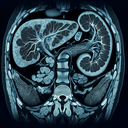

Магнітно-резонансна томографія (МРТ) органів черевної порожнини – це неінвазивний метод діагностики, який використовує магнітні поля і радіохвилі для створення детальних зображень внутрішніх структур. Цей метод дозволяє лікарям оглянути органи, такі як печінка, підшлункова залоза, селезінка, нирки, жовчний міхур та інші. Переваги МРТ черевної порожнини: 1...